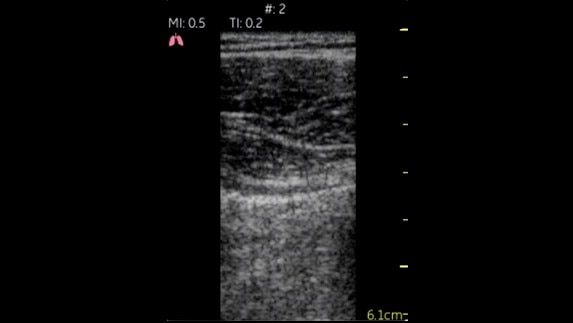

Akciğerler